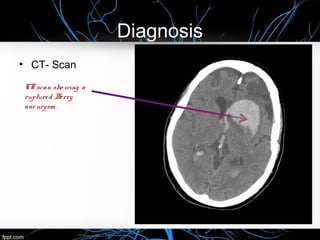

• CT- Scan

CTscan sho wing a

ruptured Berry

aneurysm.